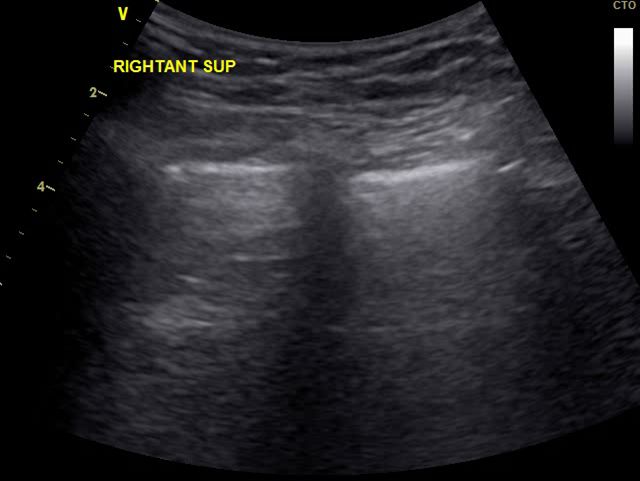

肺脏超声示肺水明显升高(图4)

图4:肺脏超声(2017-08-31)